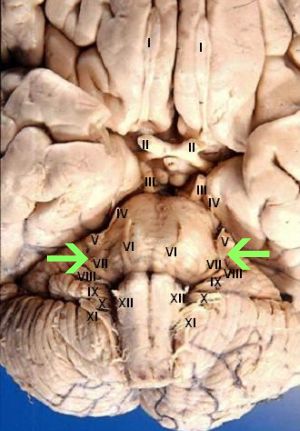

The twelve pairs of cranial nerves include:

- Olfactory

- Optic

- Oculomotor

- Trochlear

- Trigeminal

- Abducent

- Facial (indicated by the green arrows)

- Vestibulocochlear

- Glossopharyngeal

- Vagus

- Accessory

- Hypoglossal